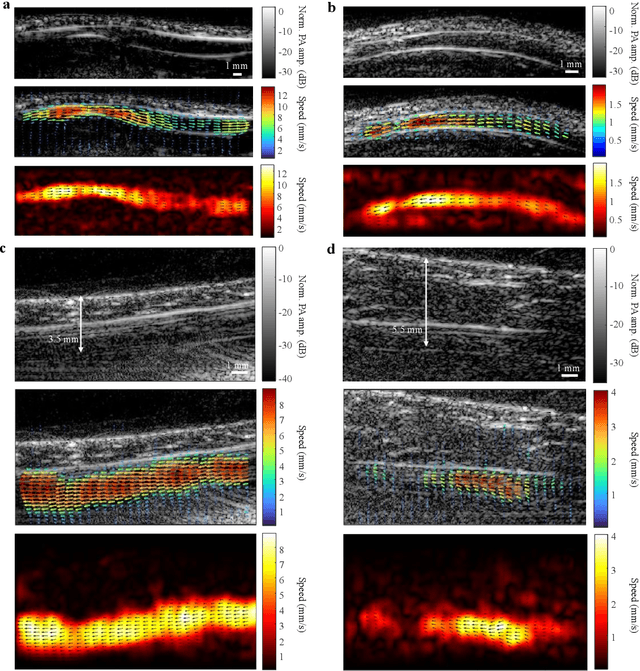

Non-invasive imaging of deep blood vessels for mapping hemodynamics remains an open quest in biomedical optical imaging. Although pure optical imaging techniques offer rich optical contrast of blood and have been reported to measure blood flow, they are generally limited to surface imaging within the optical diffusion limit of about one millimeter. Herein, we present photoacoustic vector tomography (PAVT), breaking through the optical diffusion limit to image deep blood flow with speed and direction quantification. PAVT synergizes the spatial heterogeneity of blood and the photoacoustic contrast; it compiles successive single-shot, wide-field photoacoustic images to directly visualize the frame-to-frame propagation of the blood with pixel-wise flow velocity estimation. We demonstrated in vivo that PAVT allows hemodynamic quantification of deep blood vessels at five times the optical diffusion limit (more than five millimeters), leading to vector mapping of blood flow in humans. By offering the capability for deep hemodynamic imaging with optical contrast, PAVT may become a powerful tool for monitoring and diagnosing vascular diseases and mapping circulatory system function.